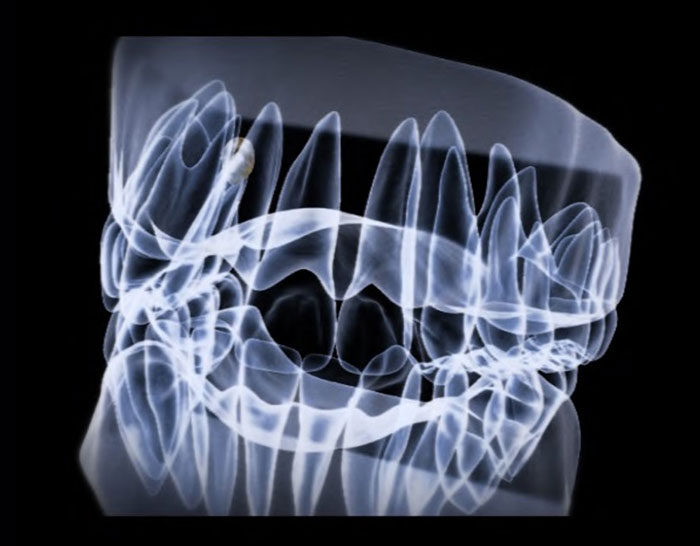

03.CTレントゲン診断

当院では、矯正治療を行うにあたってCT診断を行います。

これは骨の状態や骨に埋まっている歯の状態を比べたときに、動きやすいのか動きにくいのか、動かすことによるデメリットやリスクがあるのかどうかを判断するための、大きな重要な診査診断になってきます。

特にCT画像でわかることとして、

・歯並びや骨の中に埋まっている歯の状態

・顎の形態

・歯周病の状態

・噛み合わせの状態

・歯の根本の膿の袋の状態

など様々な症状や状態を確認することができます。

CT画像診断により、具体的な矯正治療の治療期間やリスクについてを視覚的にお伝えします。従来のレントゲンでは わからなかった、歯を支えている骨の状態や頭蓋骨の解剖学的形態をCT画像上で把握することによって、歯を並べるときに以下ができるようになりました。

●骨が邪魔をしていて、矯正治療を難しくさせていることの確認

●骨の中に埋まっている歯の歯根の形態の確認

●歯根と歯根の距離を具体的に測定する事でインビザラインをうまく活用できるかどうか判断できる

矯正治療の難易度、治療のリスクについて画像上で診断し、より安全性の高い治療をご提案します。